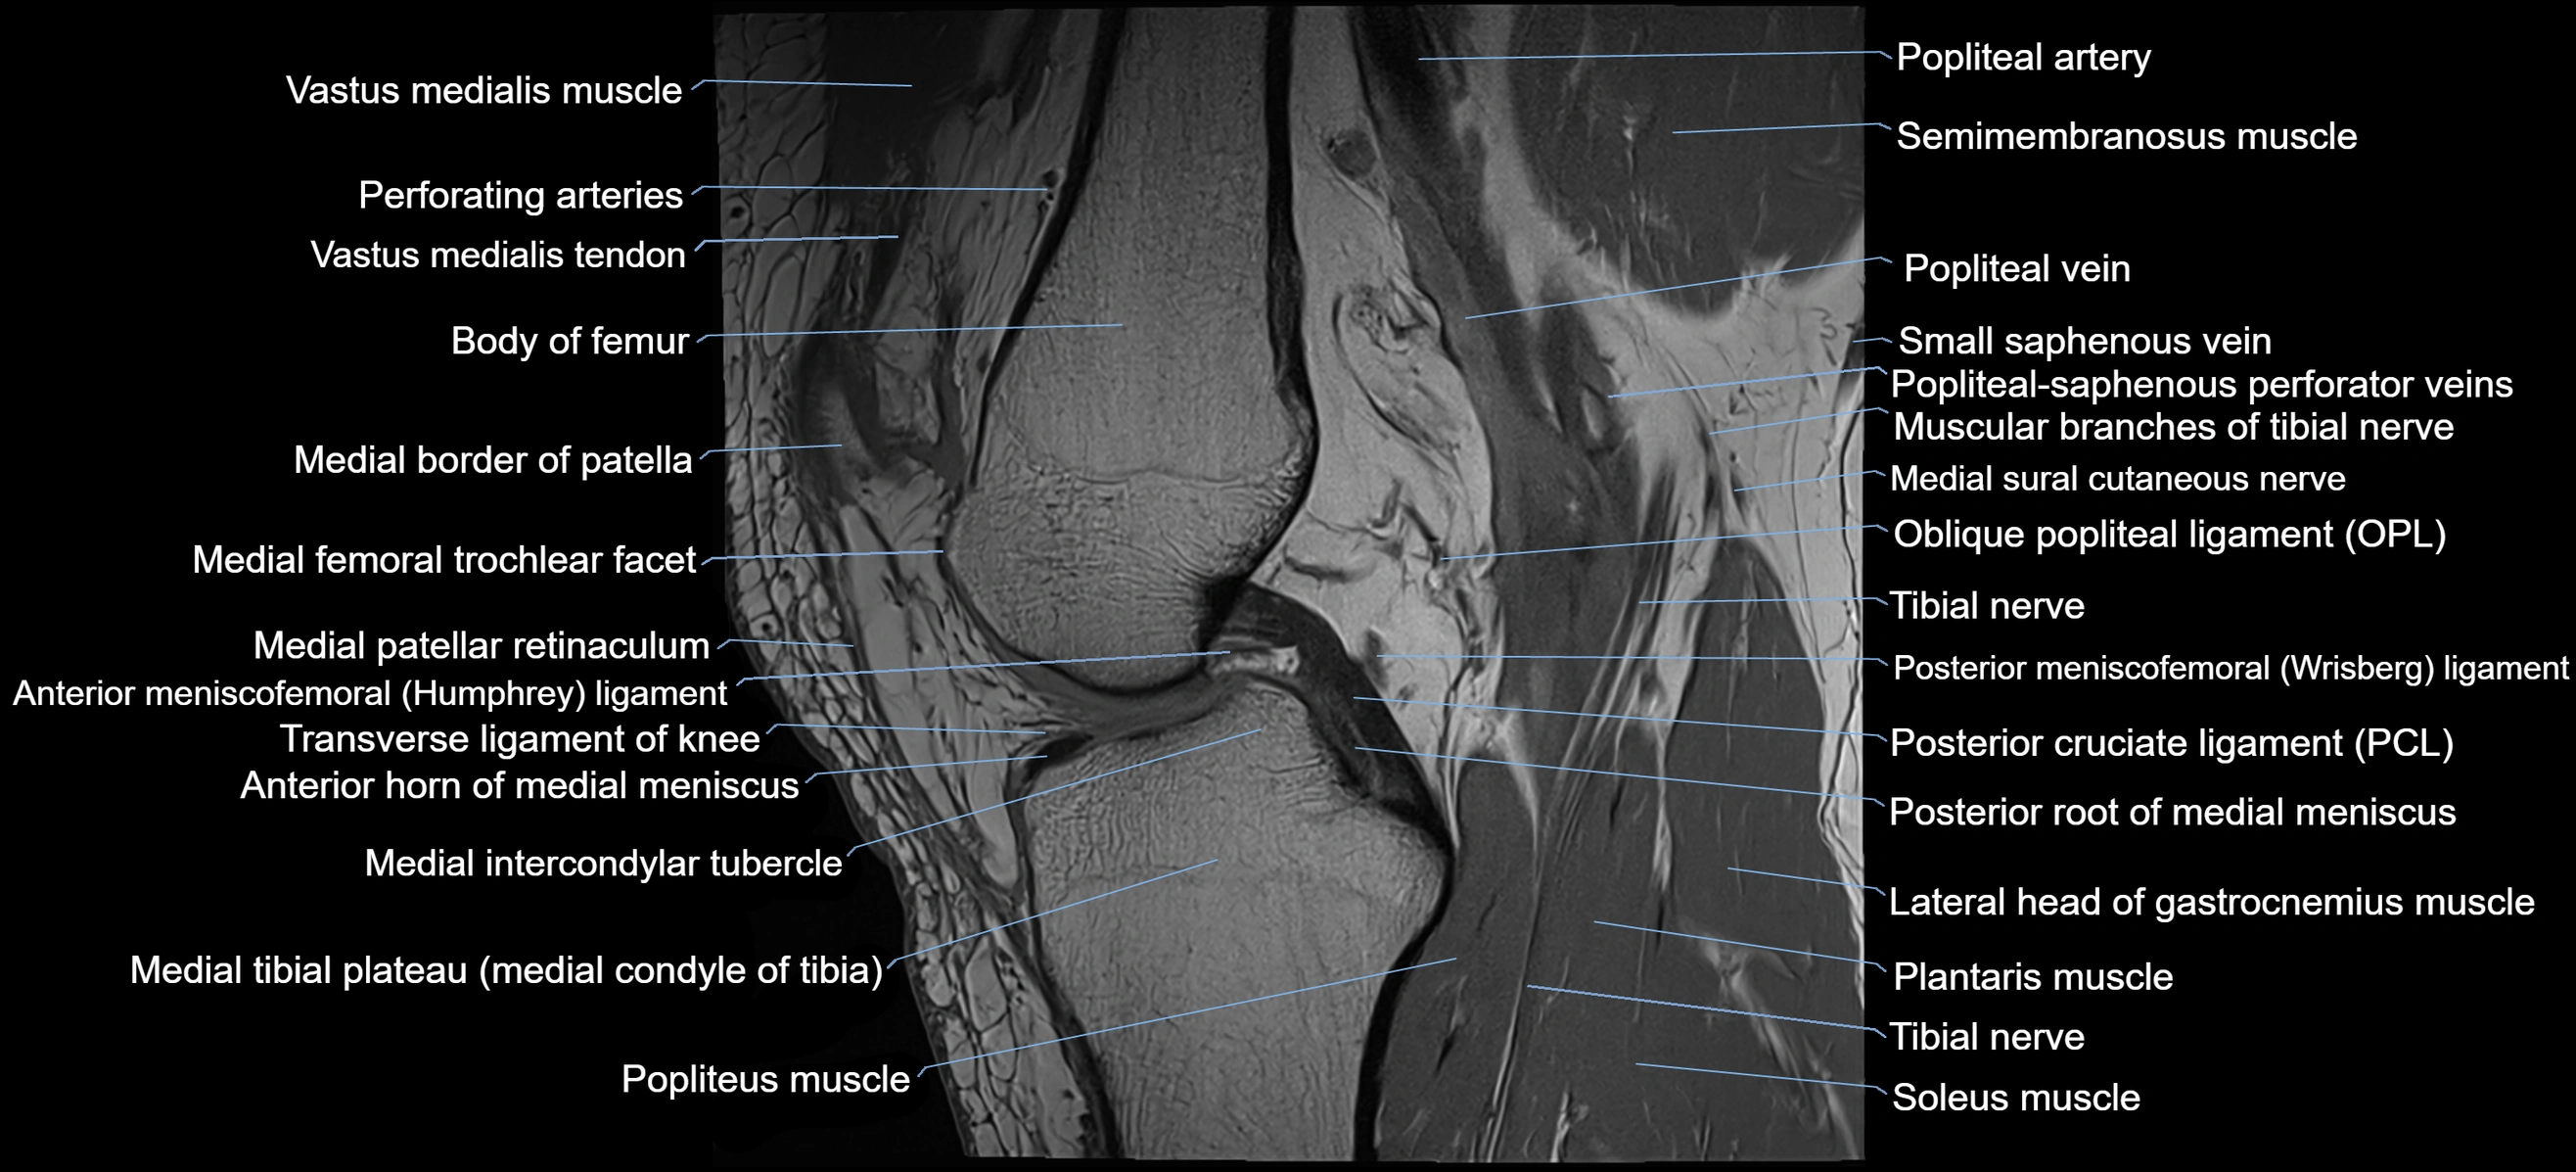

- Anterior horn of medial meniscus

- Anterior meniscofemoral ligament

- Medial border of patella

- Medial condyle of tibia

- Medial intercondylar tubercle

- Medial tibial plateau

- Oblique popliteal ligament

- Popliteal artery

- Popliteal vein

- Popliteus muscle

- Posterior cruciate ligament

- Posterior meniscofemoral ligament

- Posterior root of medial meniscus

- Semimembranosus muscle

- Soleus muscle

- Tibial nerve

- Transverse ligament of knee